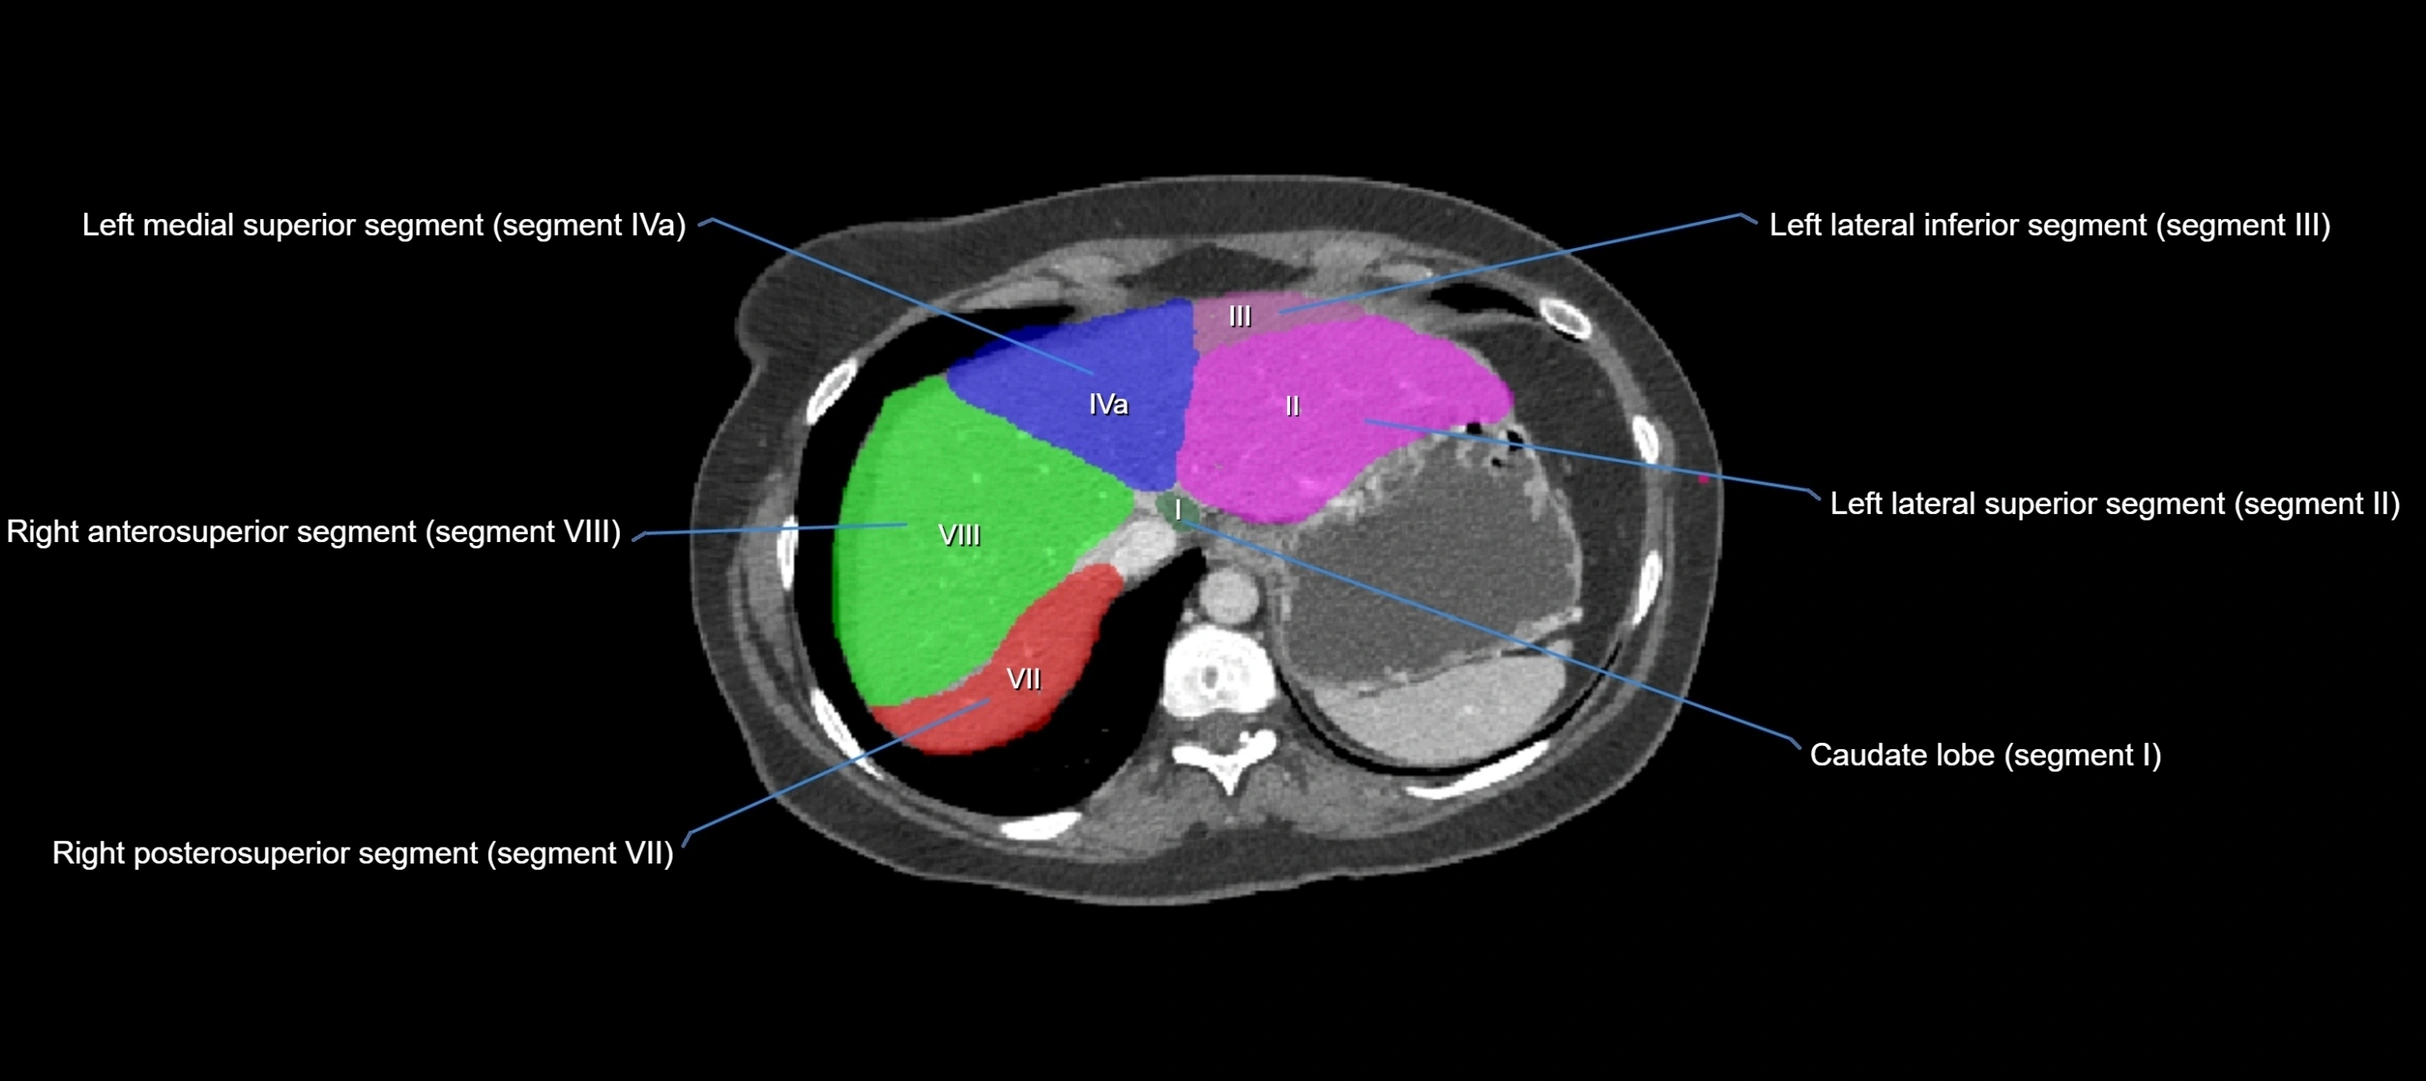

CT Image

image